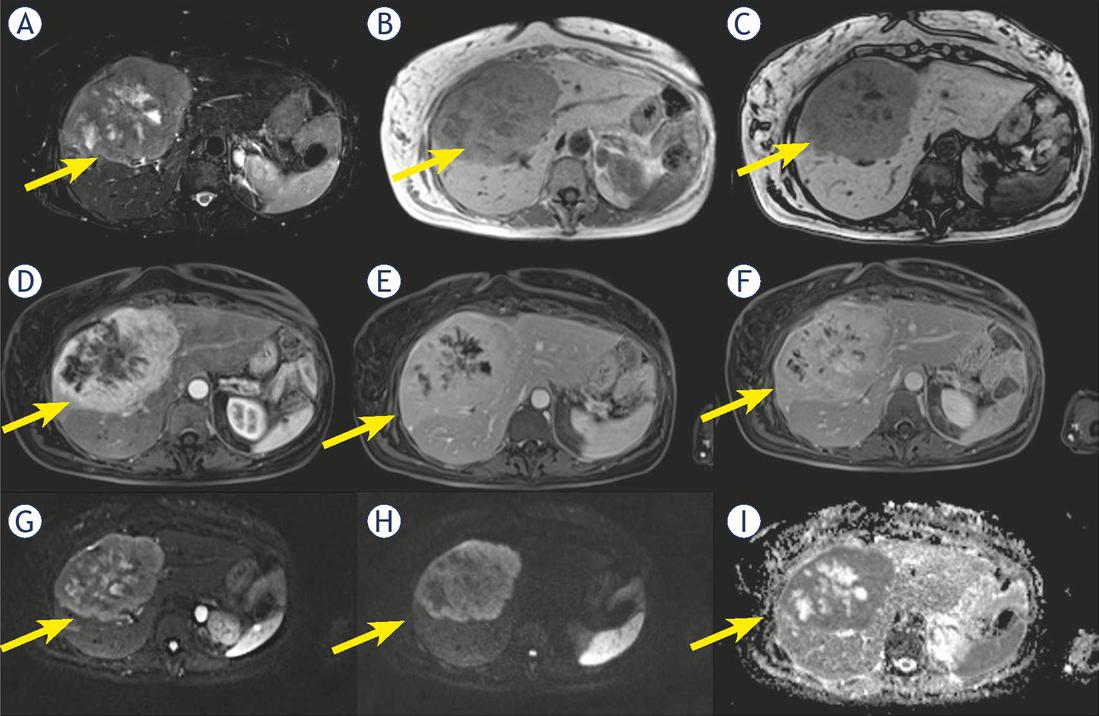

Five cHCC-CCA (714 % of cHCC-CCA) showed hyperintensity on T2-W sequences while two (28.6%) showed inhomogeneous signal in T2-W (Figure 3).

Woman 58 y with combined hepatocellular-cholangiocarcinoma (cHCC-CCA) on IV-V-VIII hepatic segment. MRI study. Pre surgical radiological diagnosis was cholangiocarcinoma (CCA). The lesion shows inhomogeneous hyperintense signal (arrow) in T2-W sequence (A) with central more hyperintense area. In T1-W in-out phase sequence (B and C) the lesion is inhomogeneous hypointense (arrow). During contrast study (D: arterial phase, E: portal phase; F: late phase) the lesion shows progressive contrast enhancement (arrow). In diffusion weighted imaging (DWI) (G, H and I) it shows restricted diffusion (arrow).

Fifteen true HCC (93.7%) had hyperintense signal on T2-W and one true HCC (6.2%) inhomogeneous signal on T2-W.